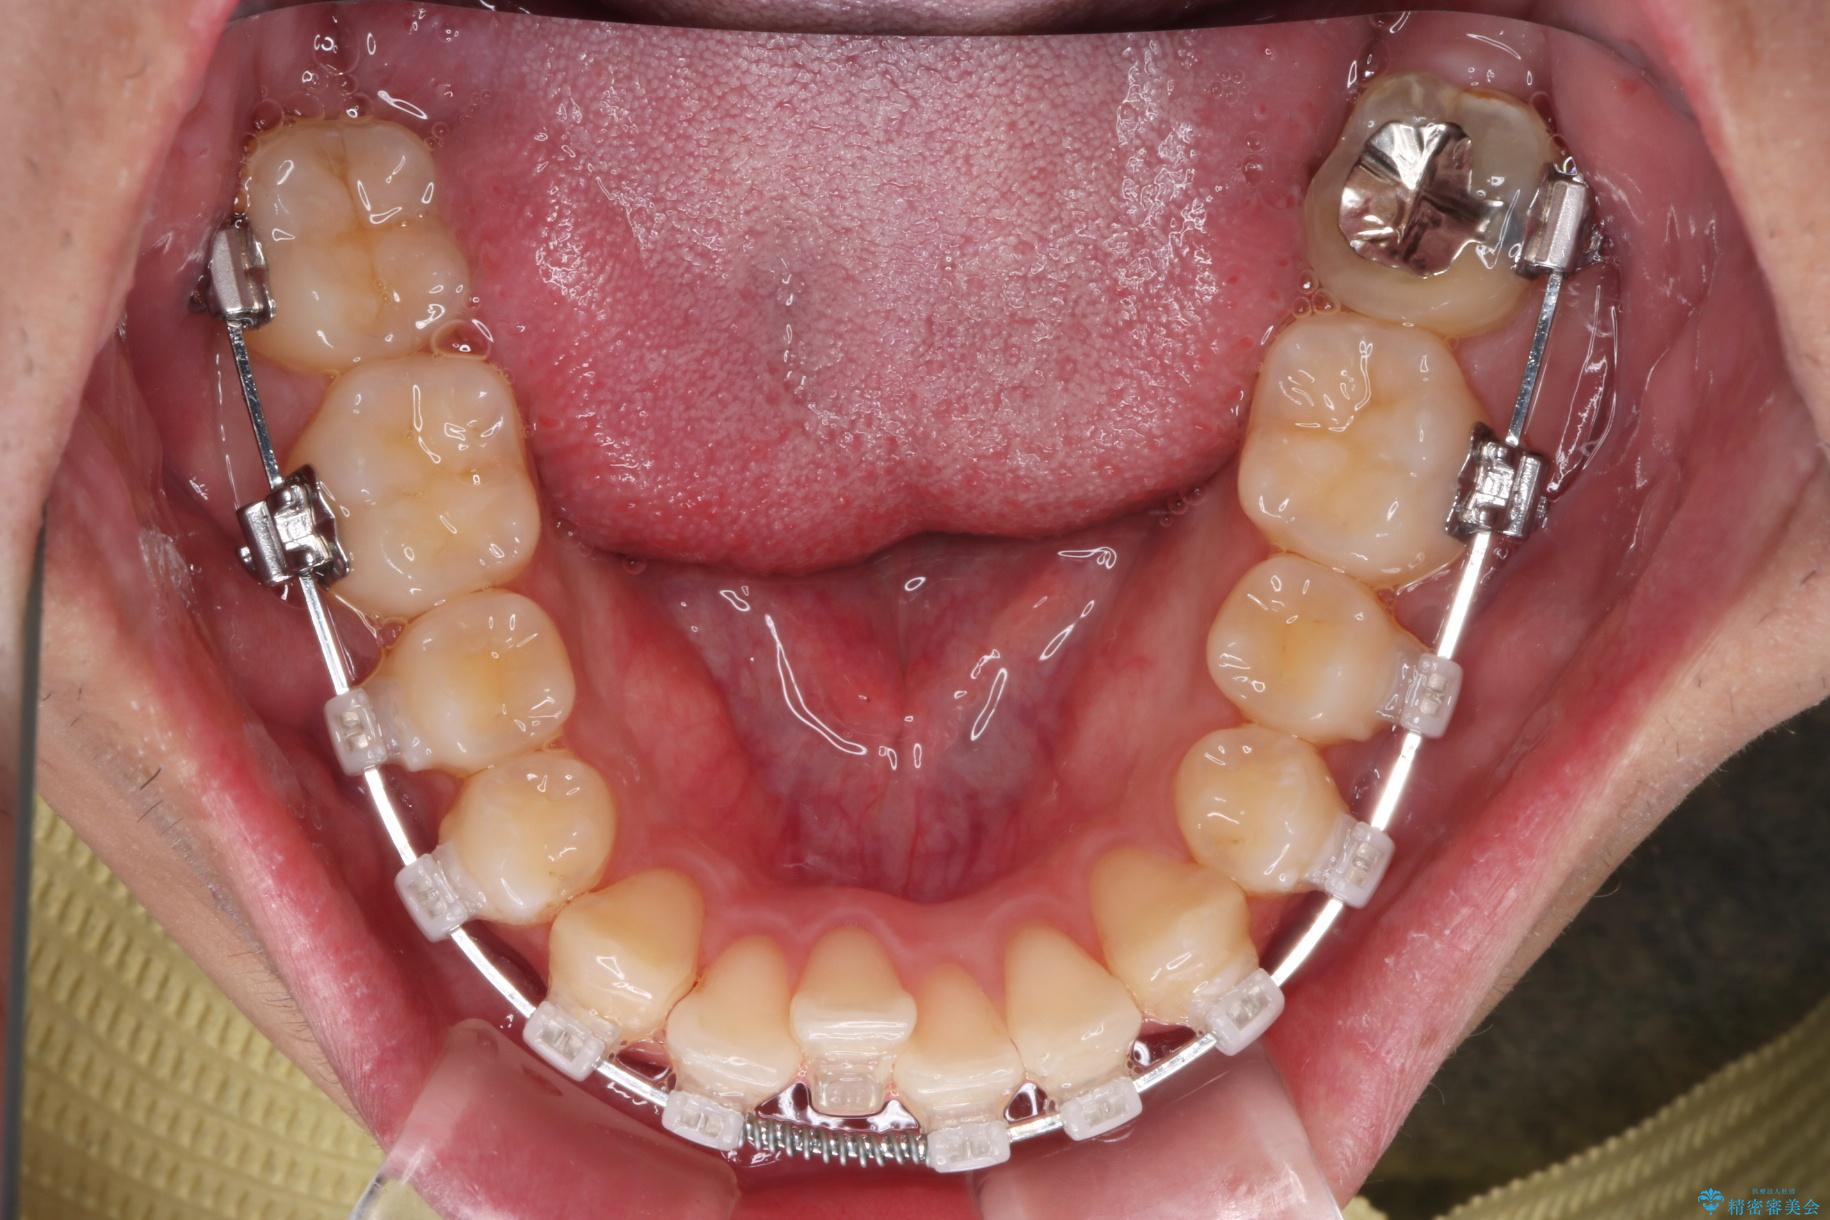

治療計画

精密検査の結果、抜歯の必要はないと判断しました。臼歯を遠心移動させ、歯列をワイヤーで整えることでスペースを確保し、IPR(歯と歯の間を削る処置)を加えて歯並びを綺麗にする治療計画を立てました。

歯の移動にオープンコイルとMI(歯肉に埋入するネジ)を用いました。